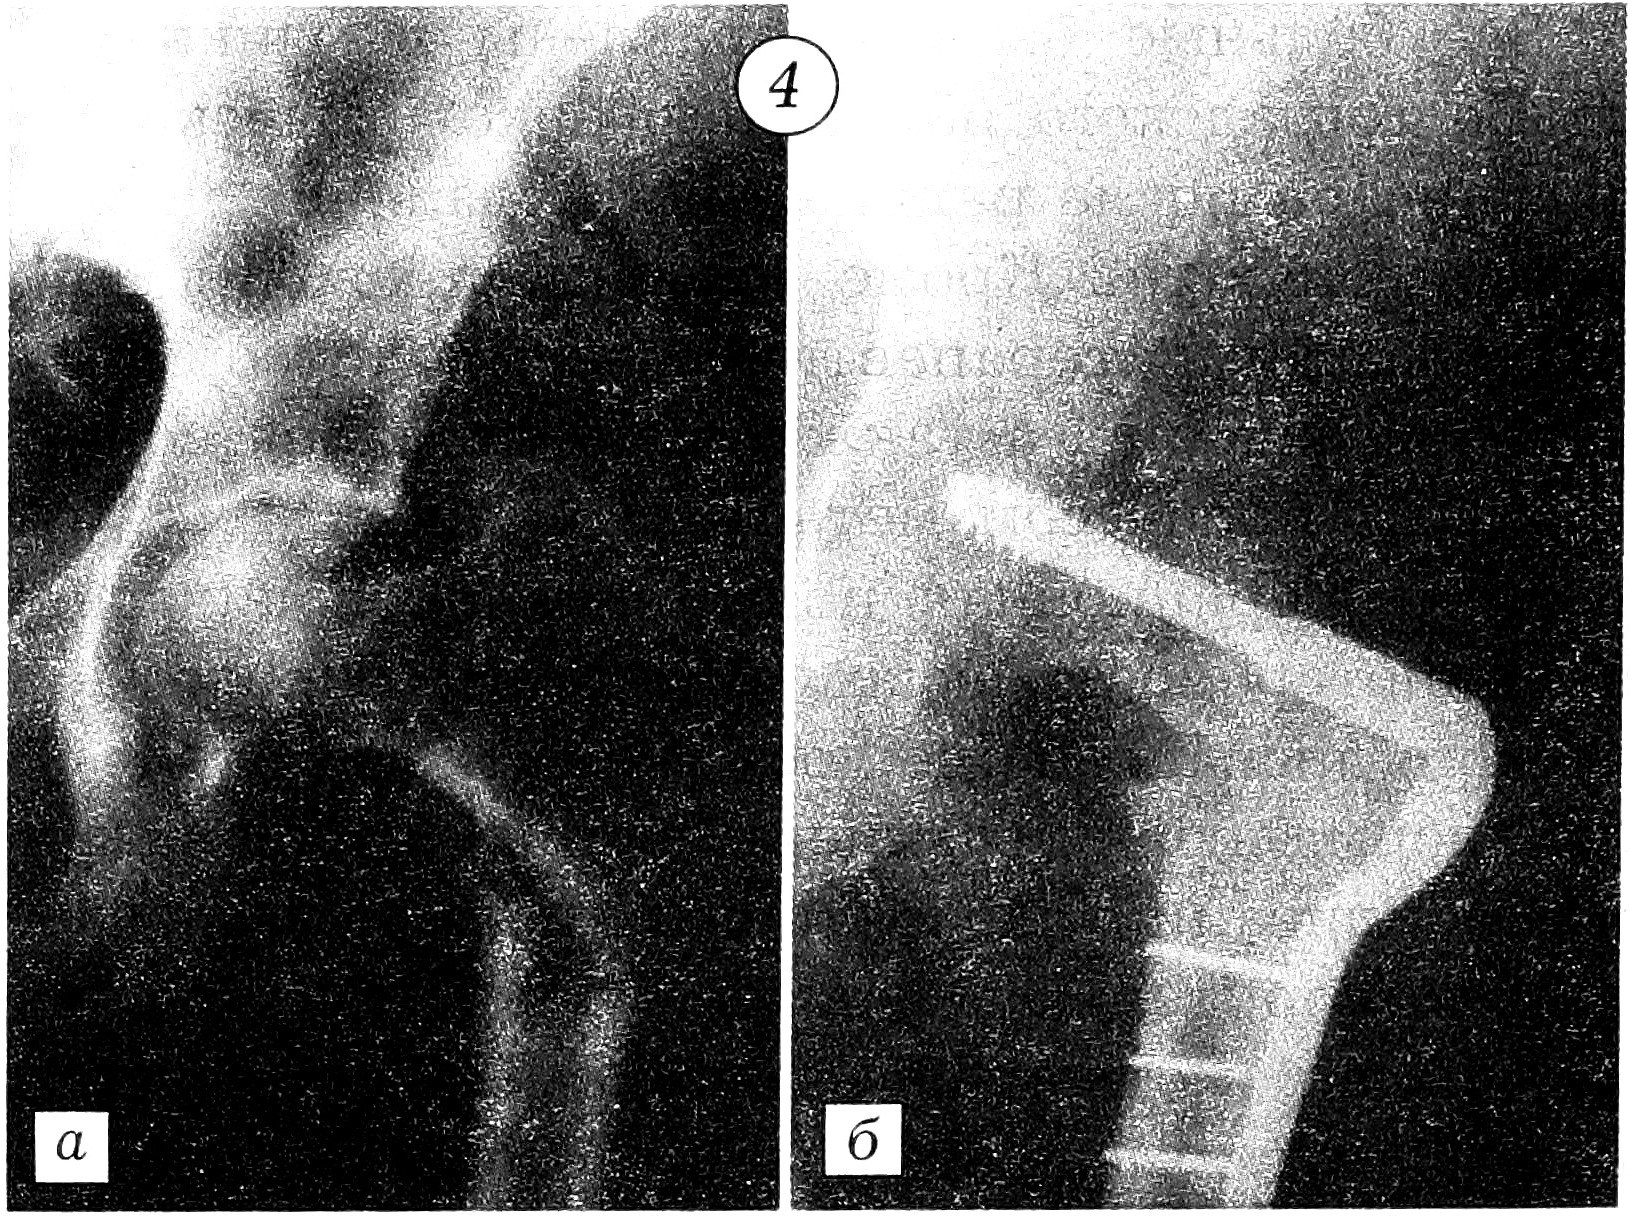

Фиксация отломков выполнялась по методике АО с применением металлоконструкций в комбинации с заполнением костного дефекта цементом [3, 5, 6]. Больной с обширным остеолитическим поражением проксимального отдела бедра произведено эндопротезирование. Поскольку ацетабулярный компонент тазобедренного сустава не был вовлечен в опухолевый процесс, выбран метод тотального эндопротезирования по Вирабову. Такая тактика снижает риск развития нестабильности сустава и необходимость повторных реконструктивных операций. При переломе диафиза плечевой кости отломки были фиксированы аппаратом Илизарова. У больного с патологическим переломом лучевой кости на фоне деструктивного остеолитического поражения, захватывающего ее дистальные 2/3, выполнена резекция патологического очага с последующим созданием синостоза культей лучевой кости с локтевой костью и артродезированием кистевого сустава длинной компрессионной пластиной АО (рис. 1). Больной с патологическим переломом головки и шейки плечевой кости после радикальной резекции метастатического остеолитического очага произведено эндопротезирование проксимального отдела плеча протезом из акрилоксида по Воронцову (рис. 2). При подвертельном переломе и переломах диафиза и шейки бедра после радикального удаления метастаза выполняли стабилизацию отломков Г-образными пластинами и конструкциями DHS с последующим заполнением образовавшегося дефекта костным цементом. В комбинации с компонентами стабилизирующих конструкций костный цемент повышает прочность фиксации (рис. 3 и 4).

Рис. 2. Рентгенограммы левой плечевой кости больной с переломом головки и шейки плеча в области метастаза рака молочной железы. a — до операции; б — после эндопротезирования по Воронцову.